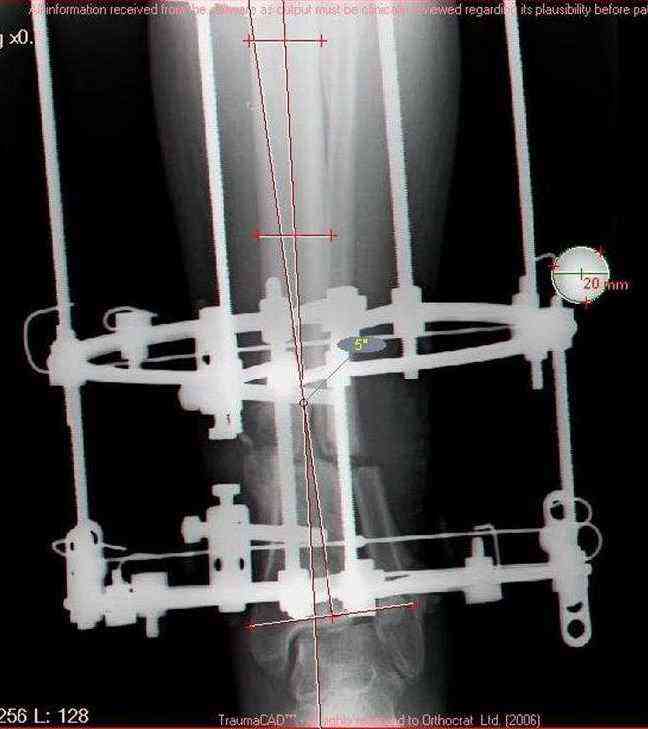

Женщина 46 лет, неудачно лечившаяся по поводу перелома голени в нижней 1\3 сначала в гипсе, поступила через 6 месяцев после остеосинтеза пластиной (рис 1). Имелась деформация в нижней 1\3 голени: варус, антекурвация, наружная ротация, два свища. Удалена пластина, дебридмент мягких тканей,

остеотомия м\б кости, аппарат Илизарова. По рентгенограммам в двух проекциях произведено планирование устранения смещений (рис 2 и 3), между вторым и третьим кольцом установлены 6 телескопических дистракторов Гесапода, данные введены в программу, и далее втечение 10 дней больная подкручивала телескопы согласно выданной компьютером инструкции. По завершению репозиции гексаподные телескопы обратно заменены на обычные штанги от аппарата Илизарова (рис 4 и 5). Еще через две недели забит гвоздь (рис 6, контроль

через 4 месяца).